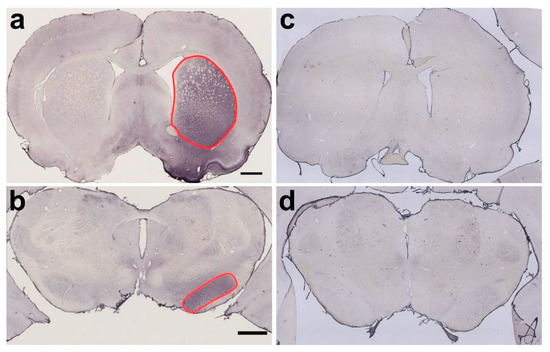

2.1. Verification of Successful BoNT-A Injection—Botulinum Neurotoxin-A-Induced Varicosities

2.3.1. Caudate-Putamen Complex (CPu)